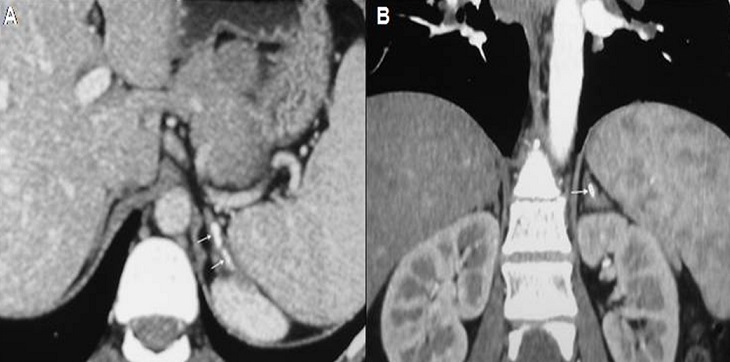

La sarcoïdose est une granulomatose systémique dont les localisations préférentielles sont les poumons, le système lymphatique et la peau. Cependant, l'atteinte des glandes endocrines est rarissime et la localisation surrénalienne est exceptionnelle. Nous rapportons l'observation d'une patiente âgée de 39 ans, sans antécédents pathologiques, adressée pour bilan étiologique d'une uvéite granulomateuse de l'oe'il gauche. A l'anamnèse, la patiente rapportait une toux sèche associée à une dyspnée d'effort, évoluant depuis 3 mois. Il n'y avait pas de notion de contage tuberculeux, ni de fièvre, ni d'altération de l'état général et ni de traumatisme abdominal. L'examen clinique était normal. Le bilan biologique montrait une hypercalcémie à 2,8 mmo/l, une hypercalciurie à 0,2 mmol /kg /24 heures et une élévation de l'enzyme de conversion de l'angiotensine à 104 UI/L (normale : 12- 68). La recherche de mycobactéries par tubage gastrique et dans les urines était négative. L'intradermo-réaction retrouvait une anergie tuberculinique et le quantiféron était négatif. Le scanner thoraco-abdominal objectivait une infiltration parenchymateuse pulmonaire faite de micronodules et de nodules pleuraux et péri-lobulaires bilatéraux prédominant dans les régions moyennes et supérieures sans atteinte fibrosante avec des adénopathies hilaires, latéro-trachéales bilatérales et sous carinaires non calcifiées, non nécrotiques et non compressives. A l'étage abdominal, il y avait des calcifications surrénaliennes gauches compatibles avec des séquelles d'atteinte granulomateuse. La biopsie de glandes salivaires montrait des lésions épithélioïdes et giganto-cellulaires sans nécrose caséeuse. La cortisolémie de base était normale (166 µg/dl). Le diagnostic de sarcoïdose systémique était retenu. Une corticothérapie à la dose de 0,5 mg/kg/j était instaurée avec une évolution favorable.